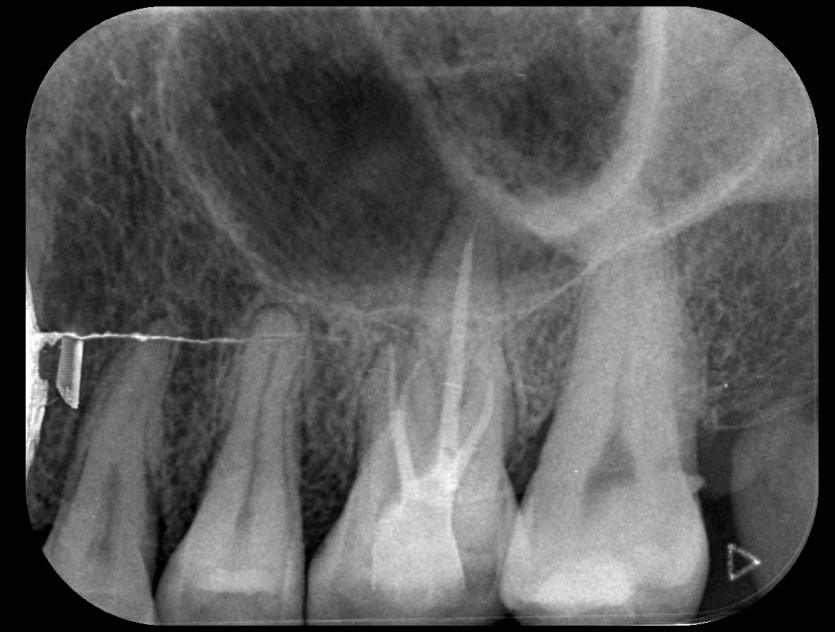

신경치료 사례